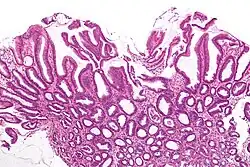

Micrograph of a reactive gastropathy. H&E stain.

Reactive gastropathy, is characterized histologically by:[2]

- Foveolar hyperplasia (black arrow), as a tortuosity in the "neck" region of the gastric glands.

- Scant or minimal inflammatory cells (white arrow), i.e. lack of large numbers of neutrophils and plasma cells..

- Smooth muscle hyperplasia in the lamina propria (in black oval).

The diagnosis is by examination of tissue, e.g. a stomach biopsy.